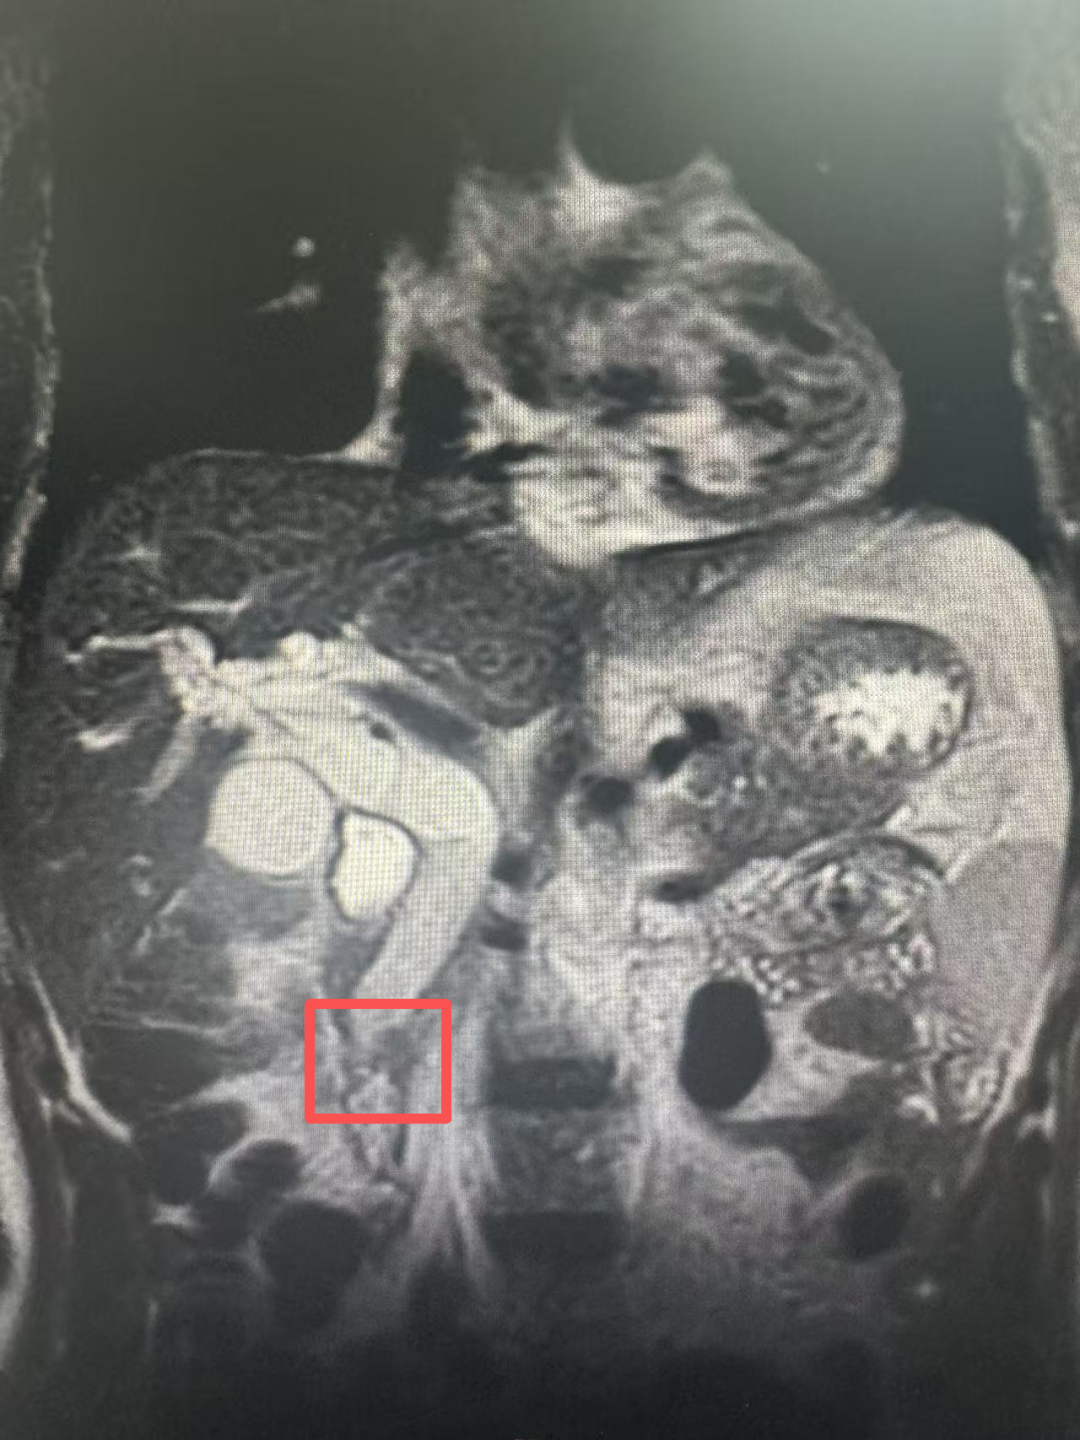

生化检验及影像学检查(增强CT及磁共振)结果证实了专家的担忧:患者总胆红素高达426.8umol/L,超过正常值20倍以上,肝脏功能已严重受损。同时,患者肝内外胆管严重扩张,胆总管下段梗阻,高度怀疑壶腹部占位性病变。

△标红处为肿瘤占位

壶腹部早期肿瘤诊断历来是难点。壶腹部解剖位置深,早期病变影像学表现不典型,就像在漫长车流里找一个小故障点,需要火眼金睛精准诊断。

在关键时刻,北大人民青岛医院启动了多学科会诊机制。北京大学人民医院肝病科饶慧瑛专家团队深入排查了可能病因,为明确诊断方向提供了重要指导。影像科专家王屹教授仔细研判影像资料,精准分析了肿瘤与周围组织的解剖关系,为手术方案的制定提供了关键依据。